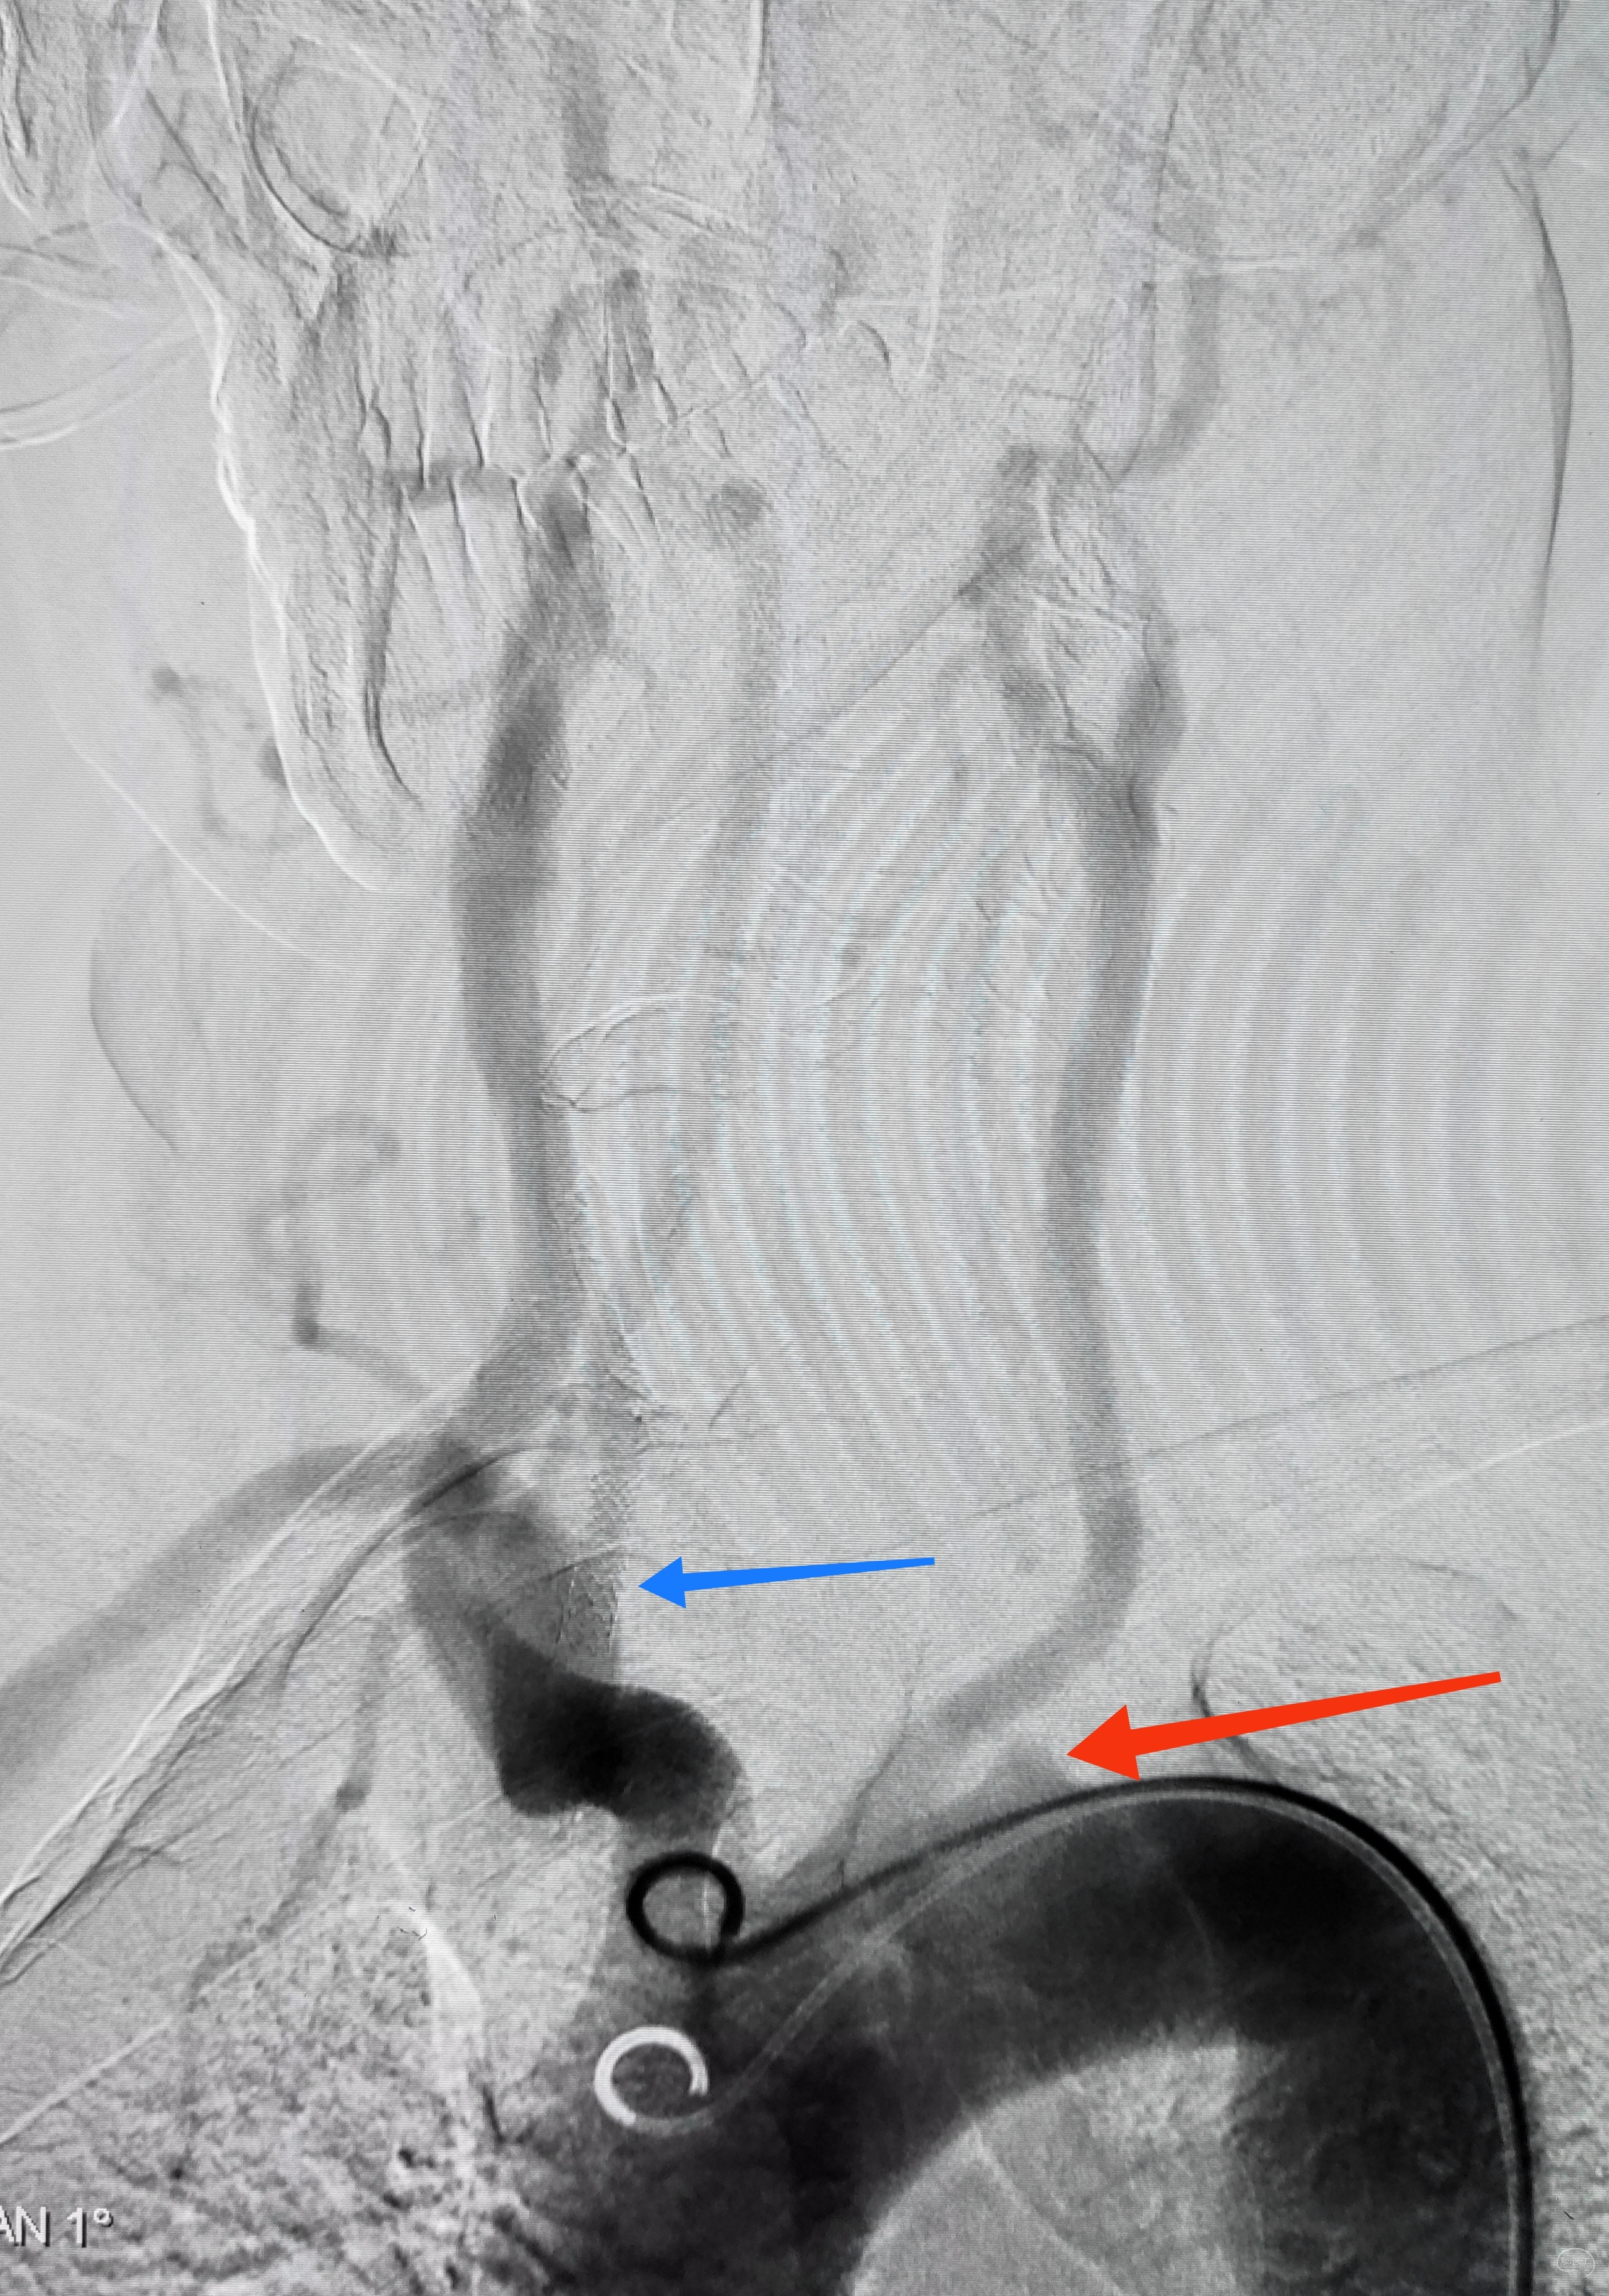

弓上造影初见:问题(一)左侧锁骨下动脉闭塞,主诉为头晕,双上肢收缩压差>20mmHg,这就是祸根?接着看弓上造影晚期像。

弓上造影晚期:剂量因素,逆流盗血隐隐可见,复合预期,那就看看对侧椎动脉情况吧

右侧锁骨下造影:右侧椎动脉开口也是重度狭窄,血流速度缓慢,闸门效应明显,此刻,不禁感叹血管的伟大,自己都狭窄得不要不要的了,还努力给对侧代偿供血,奉献精神佳!

右侧颈总动脉正侧位造影:意料之外的是,枕动脉通过肌支与右侧椎动脉吻合(紫色箭头),像极了《大风吹》的歌词“借一杯天上的水”,源源不断进行着血流的补充。但是好景不长,同侧V4段明显狭窄,无情的设置了第二道坎(绿色箭头)。

左侧颈总动脉造影:颅内床突段以远基本闭塞,仅残涓涓细流,血供极差,脑膜中动脉瘤仅少量代偿,确实不容易,这估计就是想来搭桥的初衷了吧。